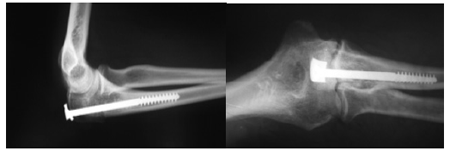

Во всех перечисленных случаях применялась дополнительная гипсовая иммобилизация от двух до четырех недель. В 22(24,4%) случаях применял-ся остеосинтез длинным губчатым компрессирую-щим винтом, из которых в 14(15,5%) случаях имел место поперечный перелом, в 5-и(5,5%) - оскольчатый (рис.2), в 3-х(3,3%) - раздробленный, двое из которых нуждались в дополнительной фиксации специально разработанной нами пластинкой и вторым винтом (рис.3).